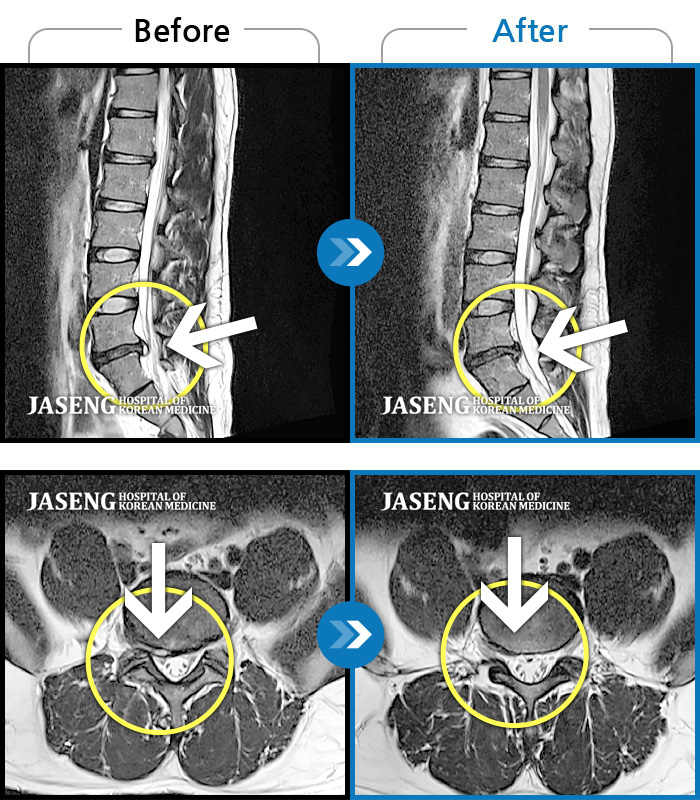

ȯںп  Ǹ   ǿ ԿǾ, ο  ġ  ۿ     Ƿ   ġḦ Ͻñ ٶϴ.